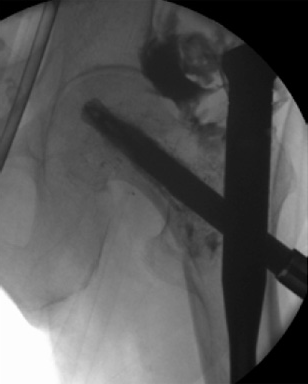

After finishing the usual procedure of inserting the nail and the perforated blade, a leakage into the joint has to be excluded by injection of contrast medium through the perforated blade first. Then the prefilled side opening cannula is inserted into the blade and the position checked by image intensifier. A medial perforation must be avoided. Furthermore, the special 1 ml syringe is adapted to the cannula (Fig 6) and the cement can be injected (Fig 7). By turning the cannula the positioning of the cement around the helical blade can be navigated. Around 36 ml of cement should be injected. The whole injection procedure must be done under image intensifier control.